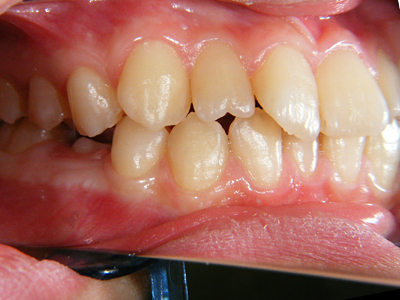

4. 術前右側

下顎前突とまでは言えませんが、上顎が明らかに下顎と比較して劣成長です。年齢的にも上顎の成長はほぼ終了し、下顎の成長は継続しますので、より顕著となり、本当に下顎前突になると考えられます。